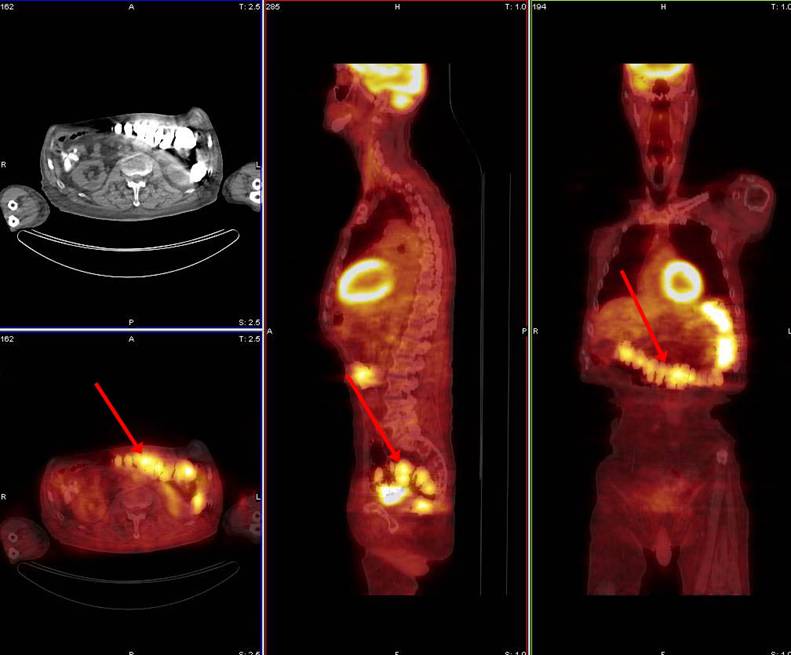

68 year old male with large B-cell lymphoma, status post six cycles of chemotherapy. PET/CT ordered for restaging.

Patient had had an upper GI barium examination one week prior to PET/CT to evaluate for nausea and vomiting. Evaluation of the abdomen and pelvis is limited by artifact created by retained barium within the colon. Careful evaluation of the non-attenuation-corrected and attenuation-corrected data sets as well as the CT data demonstrates no definite evidence for a gross abnormality in the abdomen or pelvis.

The non-attenuation-corrected data shown in the bottom row confirms that there is actually no increased activity in the region of the colon, as was apparent on the attenuation-corrected data shown in the top row. The attenuation correction process resulted in artifactually increased activity related to highly concentrated metallic density barium within the lumen of the colon.